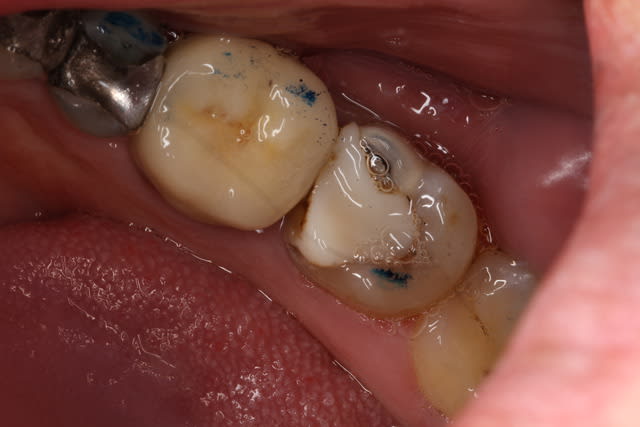

Une prep, pas encore posée :

2015 08 14 14.57 - Eugenol

2015 08 14 15.15 - Eugenol

2015 08 14 15.34 - Eugenol

2015 08 14 15.40 - Eugenol